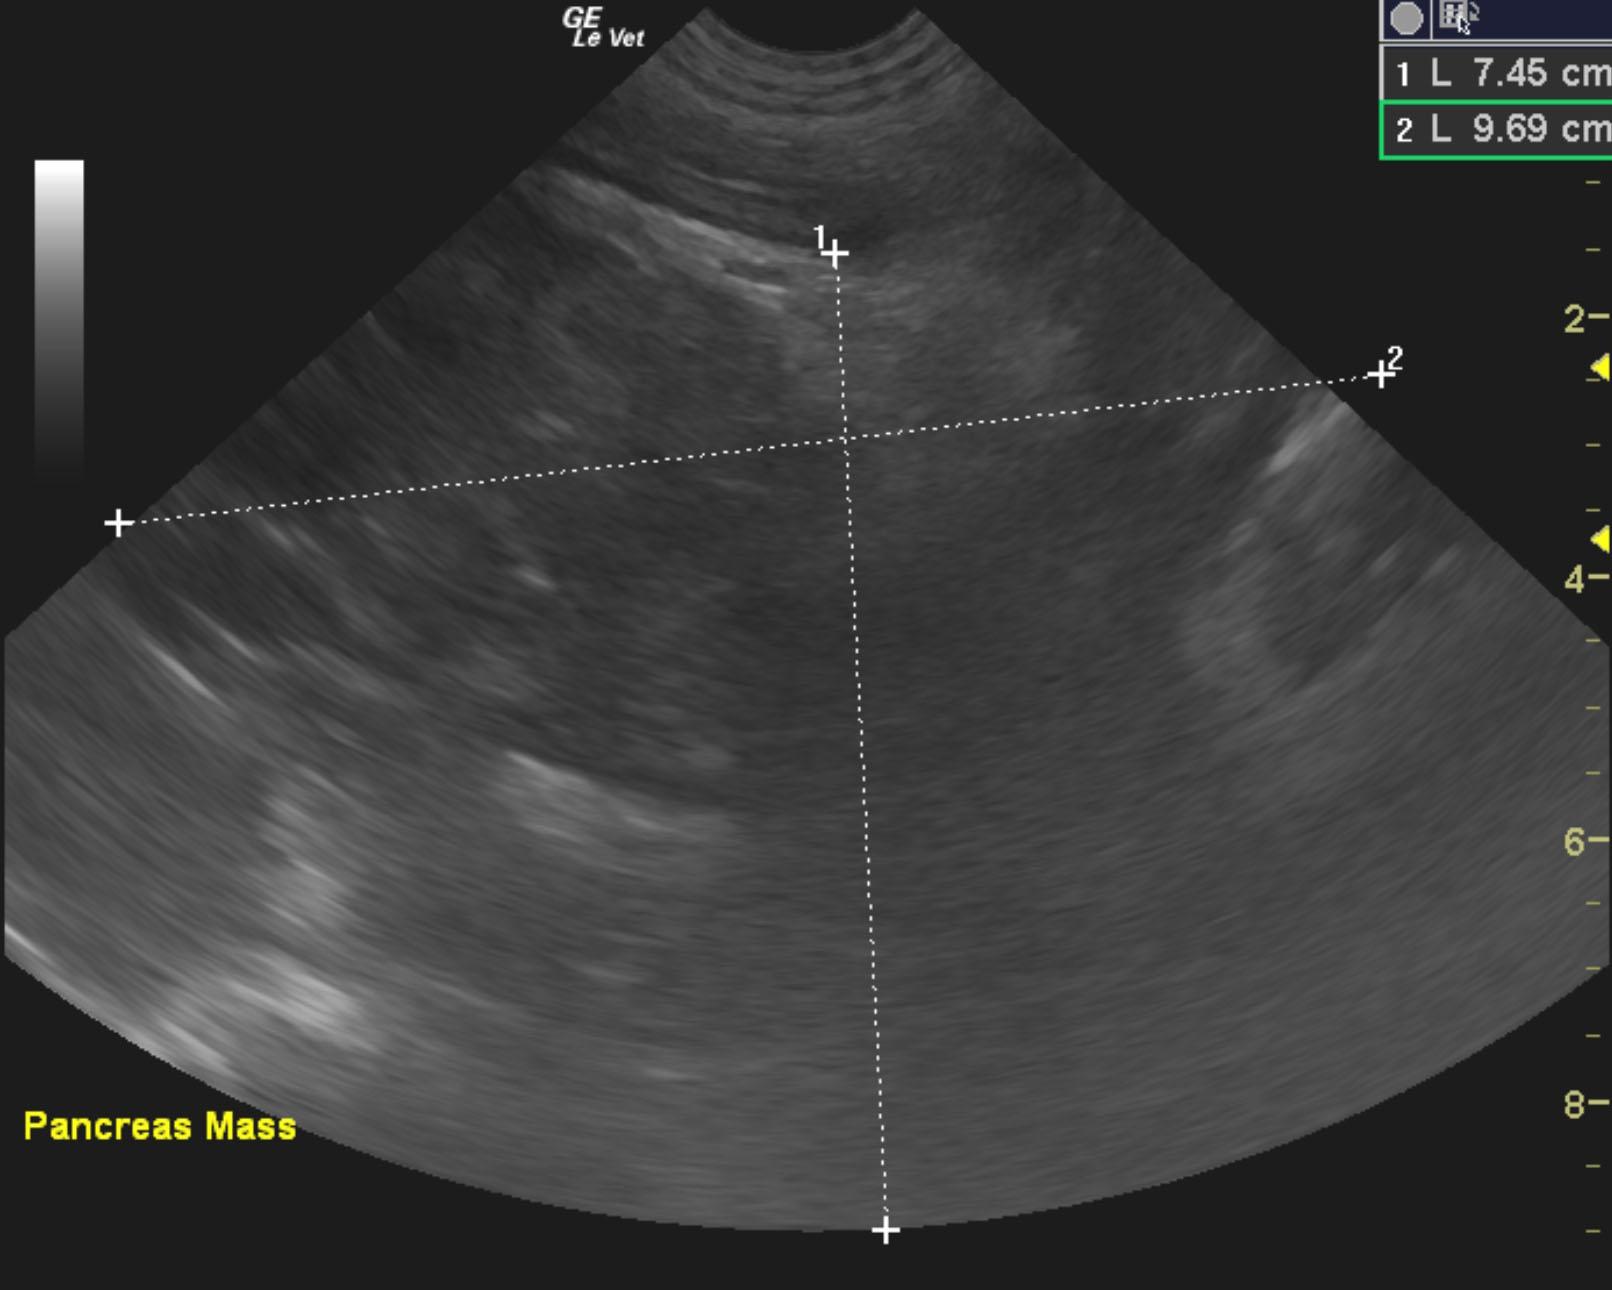

The pancreas revealed an extensive 9.7 x 7.5 cm, mixed, hypoechoic mass. The liver and spleen were riddled with multiple hypoechoic expansive nodular masses. Free fluid was noted adjacent to the spleen, which is mildly swollen. The gallbladder was unremarkable. There was also regional lymphadenopathy, with enlarged hepatic, iliac and aortic lymph nodes. Regional inflammation was noted throughout the cranial abdomen.